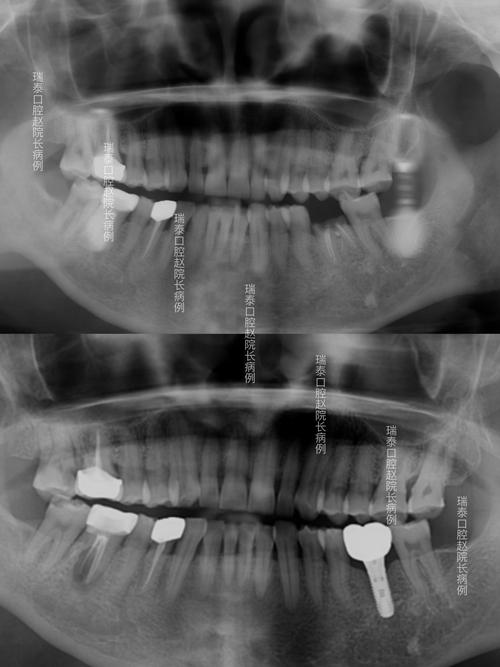

- 曲面断层片(全景片,OPG):可一次性显示全口牙齿、牙槽骨、颌骨、上颌窦、下颌神经管等结构,是种植牙前最常用的X光检查,通过曲面断层片,医生可初步判断缺牙区牙槽骨的总体高度、宽度,以及下颌神经管的走行位置(通常位于下颌骨内,距离牙槽嵴顶10-15mm)。

当X光检查提示骨量不足、解剖结构复杂(如下颌神经管位置靠近牙槽嵴、上颌窦低垂)或需进行复杂种植(如全口种植、穿颧种植)时,CT检查(尤其是口腔专用锥形束CT,CBCT)是必不可少的一步。

- 复杂病例评估:如后牙区骨量不足,需判断是否需要植骨或上颌窦提升术;上颌窦底与牙槽嵴距离小于5mm时,需设计上颌窦开窗植骨或内提升;

- 规避神经血管损伤:对于下颌后牙区种植,CBCT可精确标记下颌神经管的走行,确保种植体尖端距离神经管至少1-2mm;

- 数字化种植导板设计:基于CBCT数据,结合口内扫描模型,可制作3D打印种植导板,引导种植体精准植入预定位置,误差小于0.5mm,尤其适合全口无牙颌种植或即刻种植病例。